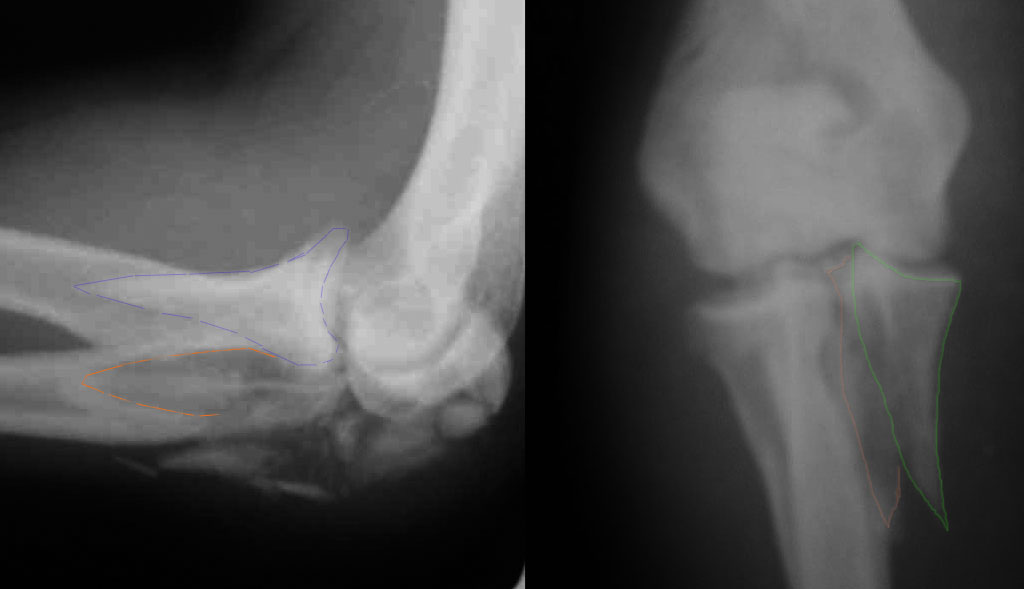

При самом большом к Вам уважении, Сергей Анатольевич, не соглашусь. У

меня, после того, как добавили "прямой" снимок, сомнений не осталось.

Венечный сломан наверняка. Но чтобы судить, насколько это критично для

стабильности, нужно иметь строго боковую проекцию. И при этом помнить,

что на него крепятся медиальные связки.

Прикрепляю снимок, где обведен фрагмент, несущий на себе венечный

отросток (весь он смещён с этим фрагментом или частично - без

качественной боковой проекции судить сложно), и отдельно на снимке

обведено "ложе", от которого он сместился.